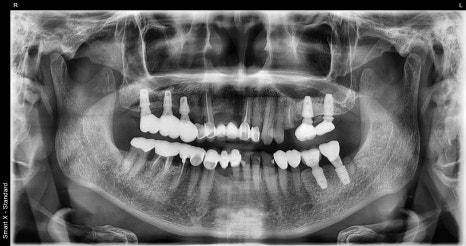

Left image: A panoramic X-ray taken at the first visit. The existing implant restoration was broken, but the root was in good condition.

Right image: #25 (the upper left second premolar) was badly decayed and only the root remained. We recommended immediate implant placement after extraction.